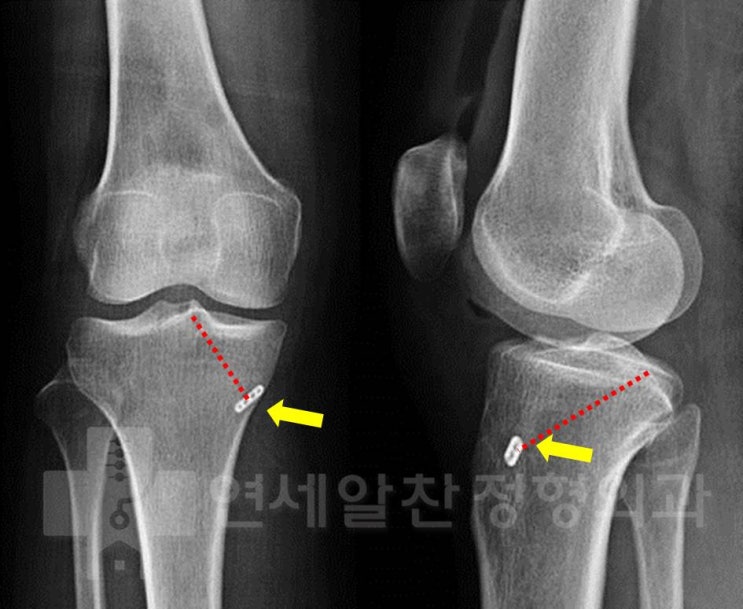

슬관절 통증의 진단에서 history taking, 이학적 검사의 중요성

50세 여자환자가 무릎 통증을 주소로 내원하였다. 환자는 2개월전 턱에 걸려 넘어지면서 무릎이 꺽이면서 ...